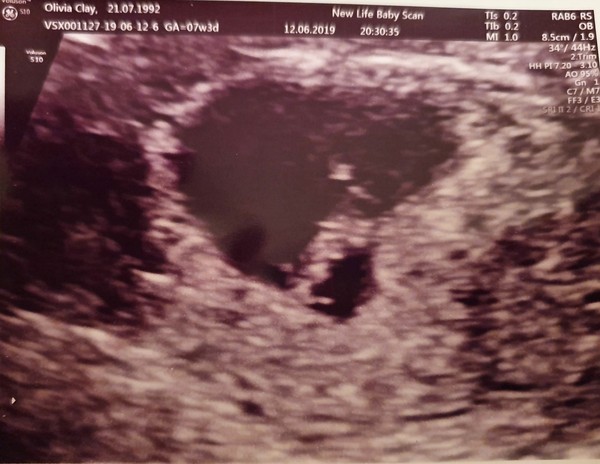

HungryPanda92 · 13/06/2019 11:32

So I had my early scan yesterday evening. All looks well so far and little blob is measuring spot on for my dates.

So glad I booked a private scan, feel like I can enjoy it a little more now. Sounds daft but I'd convinced myself there was going to be nothing there. Seeing that little heart beating away was just the best feeling.